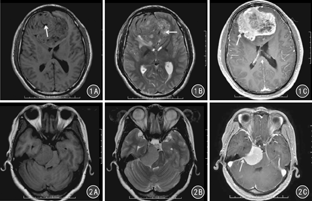

颅内HPC和脑膜瘤MRI特征表现除在增强程度上差异无统计学意义(P>0.05)外,在肿瘤的边缘及形态、肿瘤内血管流空信号、肿瘤内囊变坏死、强化方式、硬膜尾征等特征上差异均有统计学意义(P值均<0.05)。见表1。见图1、图2。

HPC属于恶性肿瘤,其细胞核异型性多、核分裂活跃,肿瘤生长速度快,且各部分生长速度不同,因此常呈分叶状。而脑膜瘤是良性肿瘤,生成缓慢,肿瘤常呈圆形、椭圆形或扁圆形。肿瘤形态上的差异,提示形态对其鉴别有一定价值,然而HPC和脑膜瘤的边界和形态特征有一定的重叠,因此在定性诊断中需要结合其他征象综合评价。本研究中,颅内HPC最大径显著大于脑膜瘤的,这可能与肿瘤的生长时间有关。

本组16例颅内HPC中11例瘤内出现粗大的血管流空信号,而95例脑膜瘤中有84例(88.4%)瘤内未发现血管流空信号,差异有统计学意义(P<0.01)。曹代荣等[4]研究发现,CTA显示颅内HPC肿块内部见多发粗大的供血动脉及颈内动脉参与供血,而脑膜瘤内则未见粗大血管。DSA术中出现多发螺旋状供血动脉为HPC特征性表现;镜下HPC内见有大量"鹿角"状血管,有的血管扩张成血窦样,有的挤压呈裂隙状;而脑膜瘤内血管小,壁薄,不同于HPC内的血管结构。因此,瘤内是否出现血管流空信号对颅内HPC的诊断及与脑膜瘤的鉴别具有较高的可靠性。

本组资料中,颅内HPC中13/16瘤内出现囊变坏死、14/16呈不均匀强化;71.6%(68/95)脑膜瘤肿瘤信号均匀、瘤内未出现囊变坏死、57.9%(55/95)呈均匀强化,差异均有统计学意义(P值均<0.01)。本组研究结果与尚海龙等[5]报道基本一致。颅内HPC具有恶性潜能,其生长速度快、侵袭性生长、丰富的供血血管中存在不成熟的血管,所以易发生囊变、坏死出血[6]。肿瘤中出现出血、坏死、囊变,其MR信号必然不均匀,同时囊变坏死区不强化,增强后肿瘤即表现为不均匀性强化。而脑膜瘤生长速度缓慢,肿瘤血管较成熟,因此肿瘤内出血、坏死囊变少见,多表现为均匀性强化。

硬膜尾征形成一方面是由于硬脑膜受到肿瘤长时间的刺激与侵袭,从而反应性增厚、纤维细胞和毛细血管增殖而生成;另一方面亦可因肿瘤通过硬膜延伸而引起。本组资料中76.8%(73/95)的脑膜瘤可见硬膜尾征,而11/16的颅内HPC中未见硬膜尾征,差异有统计学意义。脑膜瘤中出现硬膜尾征的频率较高也符合其生长缓慢的特点;而HPC生长速度快、生长时间短,对硬膜刺激还无法形成脑膜尾征[7]。潘锋等[8]研究认为,硬膜尾征对颅内HPC与脑膜瘤鉴别无统计学意义(P>0.05),与本组统计结果存在差异,可能与样本的数量或病例分析的标准不同有关。